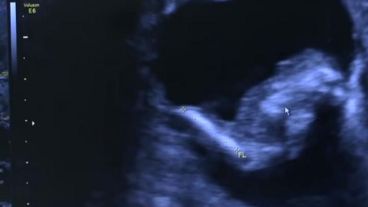

De acuerdo a lo que publicó el diario Página 12, durante su séptimo mes de embarazo, una mujer llamada Mónica Vega se realizó una ecografía de rutina en Barranquillas. Fue entonces que se detectó que dentro del feto que se estaba gestando en su vientre había otro feto, más pequeño pero con cordón umbilical y líquido amniótico.